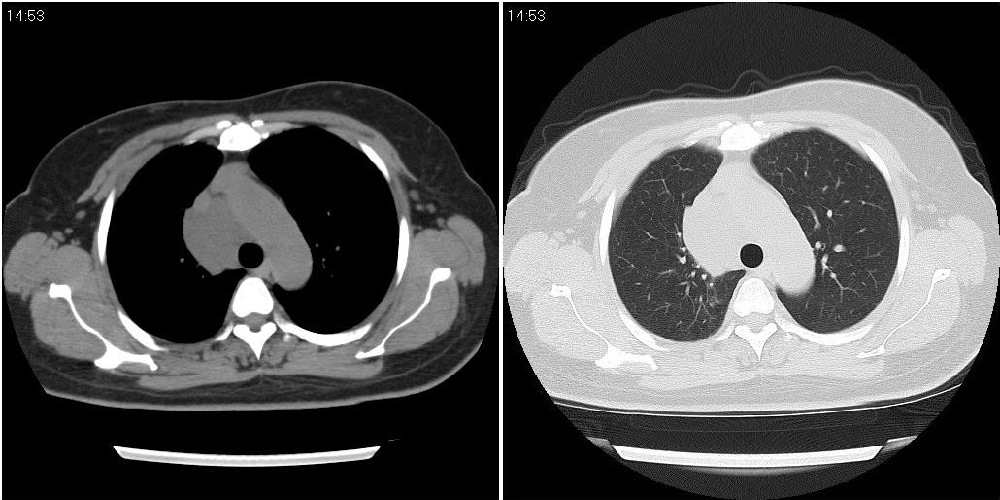

标题: CT24795:女性,47岁,右下腿静脉静脉曲张手术前体检,发现 [打印本页]

标题: CT24795:女性,47岁,右下腿静脉静脉曲张手术前体检,发现

囊性无明显占位效应:1淋巴管囊肿2畸胎瘤(其上部见小钙化)3前肠囊肿

右上纵隔囊性占位性病变;考虑淋巴管囊肿,不排除支气管囊肿。

支气管囊肿、囊性畸胎瘤、肠源性囊肿均有可能。

右上纵隔囊性占位性病变;考虑淋巴管囊肿,不排除支气管囊肿。 建议增强。

考虑淋巴管囊肿,不排除前肠囊肿。